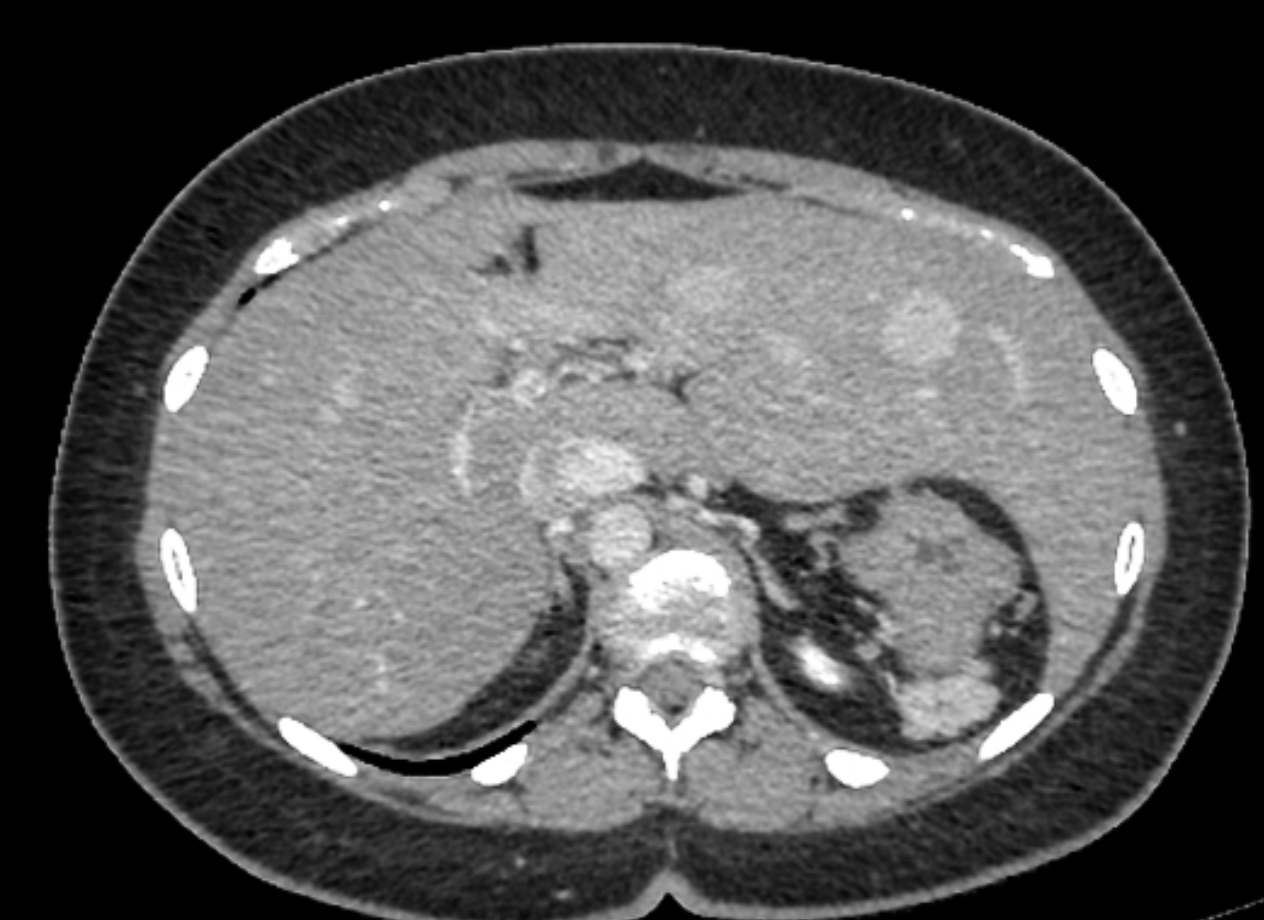

There is inversion of some abdominal structures (liver, spleen and stomach) with thoracic structures in normal position. Multiple splenules are seen on right hypochondrium. The study protocol was made for chest CT.

Case Discussion

Situs inversus partialis refers to any kind of incomplete organs inversion, like in this case. Malformations associations are more frequent in situs inversus partialis than in situs inversus totalis.